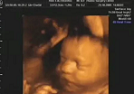

ЗD УЗИ – чрезвычайно важная диагностическая процедура, позволяющая на ранних сроках беременности выявить наличие патологий развития плода. Врачи рекомендуют проводить это исследование, начиная с 5-й недели, однако при угрозе прерывания или других показаниях, трехмерное УЗИ могут порекомендовать и на более ранних сроках.

Современные аппараты за счет более четкого трехмерного изображения дают возможность специалистам на ранних сроках выявить патологии плода и своевременно изменить тактику ведения беременности, что благотворно сказывается на развитии плода.

Трехмерное УЗИ выдает совершенно новую картинку. Прежде всего, изображение объемное и цветное. Мама имеет возможность познакомиться со своим малышом еще во время беременности. Цены узнавайте у лечащего врача.